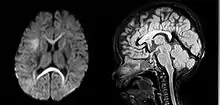

Tomografia computadorizada de um sangramento intracerebral espontâneo, vazamento nos ventrículos laterais

As causas incluem o traumatismo cerebral, aneurismas, malformações arteriovenosas e tumores cerebrais.[3] Os maiores fatores de risco para hemorragia espontânea são a pressão arterial elevada e a amiloidose. Outros fatores de risco incluem alcoolismo, colesterol baixo, anticoagulantes e cocaína.[2] O diagnóstico é tipicamente por tomografia computadorizada. Outras condições que podem ocorrer de forma semelhante incluem o acidente vascular cerebral isquêmico.[3]

A hemorragia intraparenquimatosa pode ser reconhecida na tomografia computadorizada porque o sangue aparece mais brilhante do que outro tecido e é separado da mesa interna do crânio por tecido cerebral. O tecido que envolve um sangramento é muitas vezes menos denso do que o resto do cérebro por causa do edema e, portanto, aparece mais escuro na tomografia computadorizada.[14]